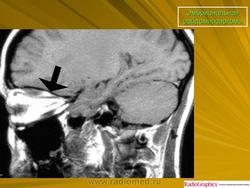

Рабдомиосаркома — чрезвычайно агрессивная опухоль орбиты, является наиболее частой причиной злокачественного роста в орбите у детей. Мальчики болеют почти в 2 раза чаще. Источником роста рабдомиосаркомы являются клетки скелетных мышц. Выделены три типа опухоли: эмбриональный, альвеолярный и плеоморфный, или дифференцированный. Последний тип встречается редко. У детей до 5 лет чаще развивается эмбриональный тип опухоли, после 5 лет — альвеолярный. Как правило, рабдомиосаркома состоит из элементов нескольких типов (смешанный вариант). Точный диагноз можно установить только на основании результатов электронной микроскопии.

Излюбленная локализация опухоли — верхневнутренний квадрант орбиты, поэтому в процесс рано вовлекаются мышца, поднимающая верхнее веко, и верхняя прямая мышца. Птоз, ограничение движений глаза, смещение его книзу и книзу кнутри — это первые признаки, на которые обращают внимание как сами больные, так и окружающие лица. У детей экзофтальм или смещение глаза при локализации опухоли в переднем отделе орбиты развивается в течение нескольких недель (рис. 20.23, а). У взрослых опухоль растет медленнее, в течение нескольких месяцев. Быстрое увеличение экзофтальма сопровождается появлением застойных изменений в эписклеральных венах, глазная щель полностью не смыкается, отмечаются инфильтраты на роговице и ее изъязвление. На глазном дне — застойный диск зрительного нерва. Первично развиваясь вблизи верхневнутренней стенки орбиты, опухоль быстро разрушает прилежащую тонкую костную стенку, прорастает в полость носа, вызывая носовые кровотечения. Ультразвуковое сканирование, компьютерная томография, термография и тонкоигольная аспирационная биопсия — это оптимальный диагностический комплекс инструментальных методов исследования при рабдомиосаркоме (рис. 20.23, б). Лечение комбинированное. Протокол лечения предусматривает предварительное проведение полихимиотерапии в течение 2 нед, после чего проводят наружное облучение орбиты. После комбинированного лечения более 3 лет живут 71 % больных.